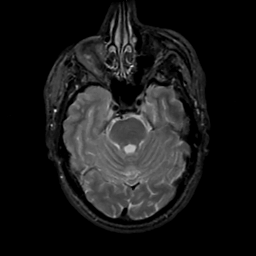

MR Study #2, February 17, 1991 -- Slice #15